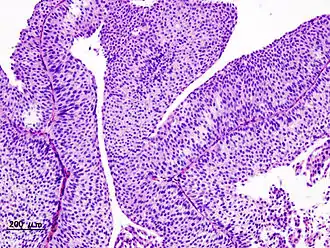

Microscopisch beeld van blaaskanker T1

- T1 : de tumor is ingegroeid in het bindweefsel van het slijmvlies van de blaas.